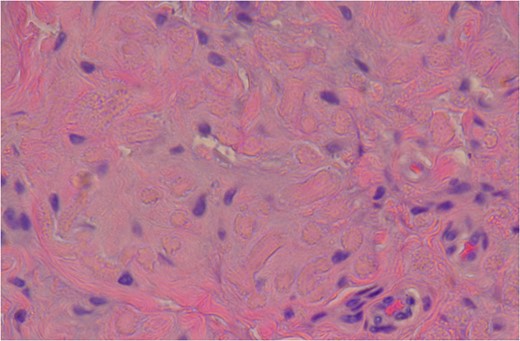

High Power slide showing elastic fibres (pink areas) which confirms the diagnosis of elastofibroma. (Altered elastic fibres in a collagenous matrix).